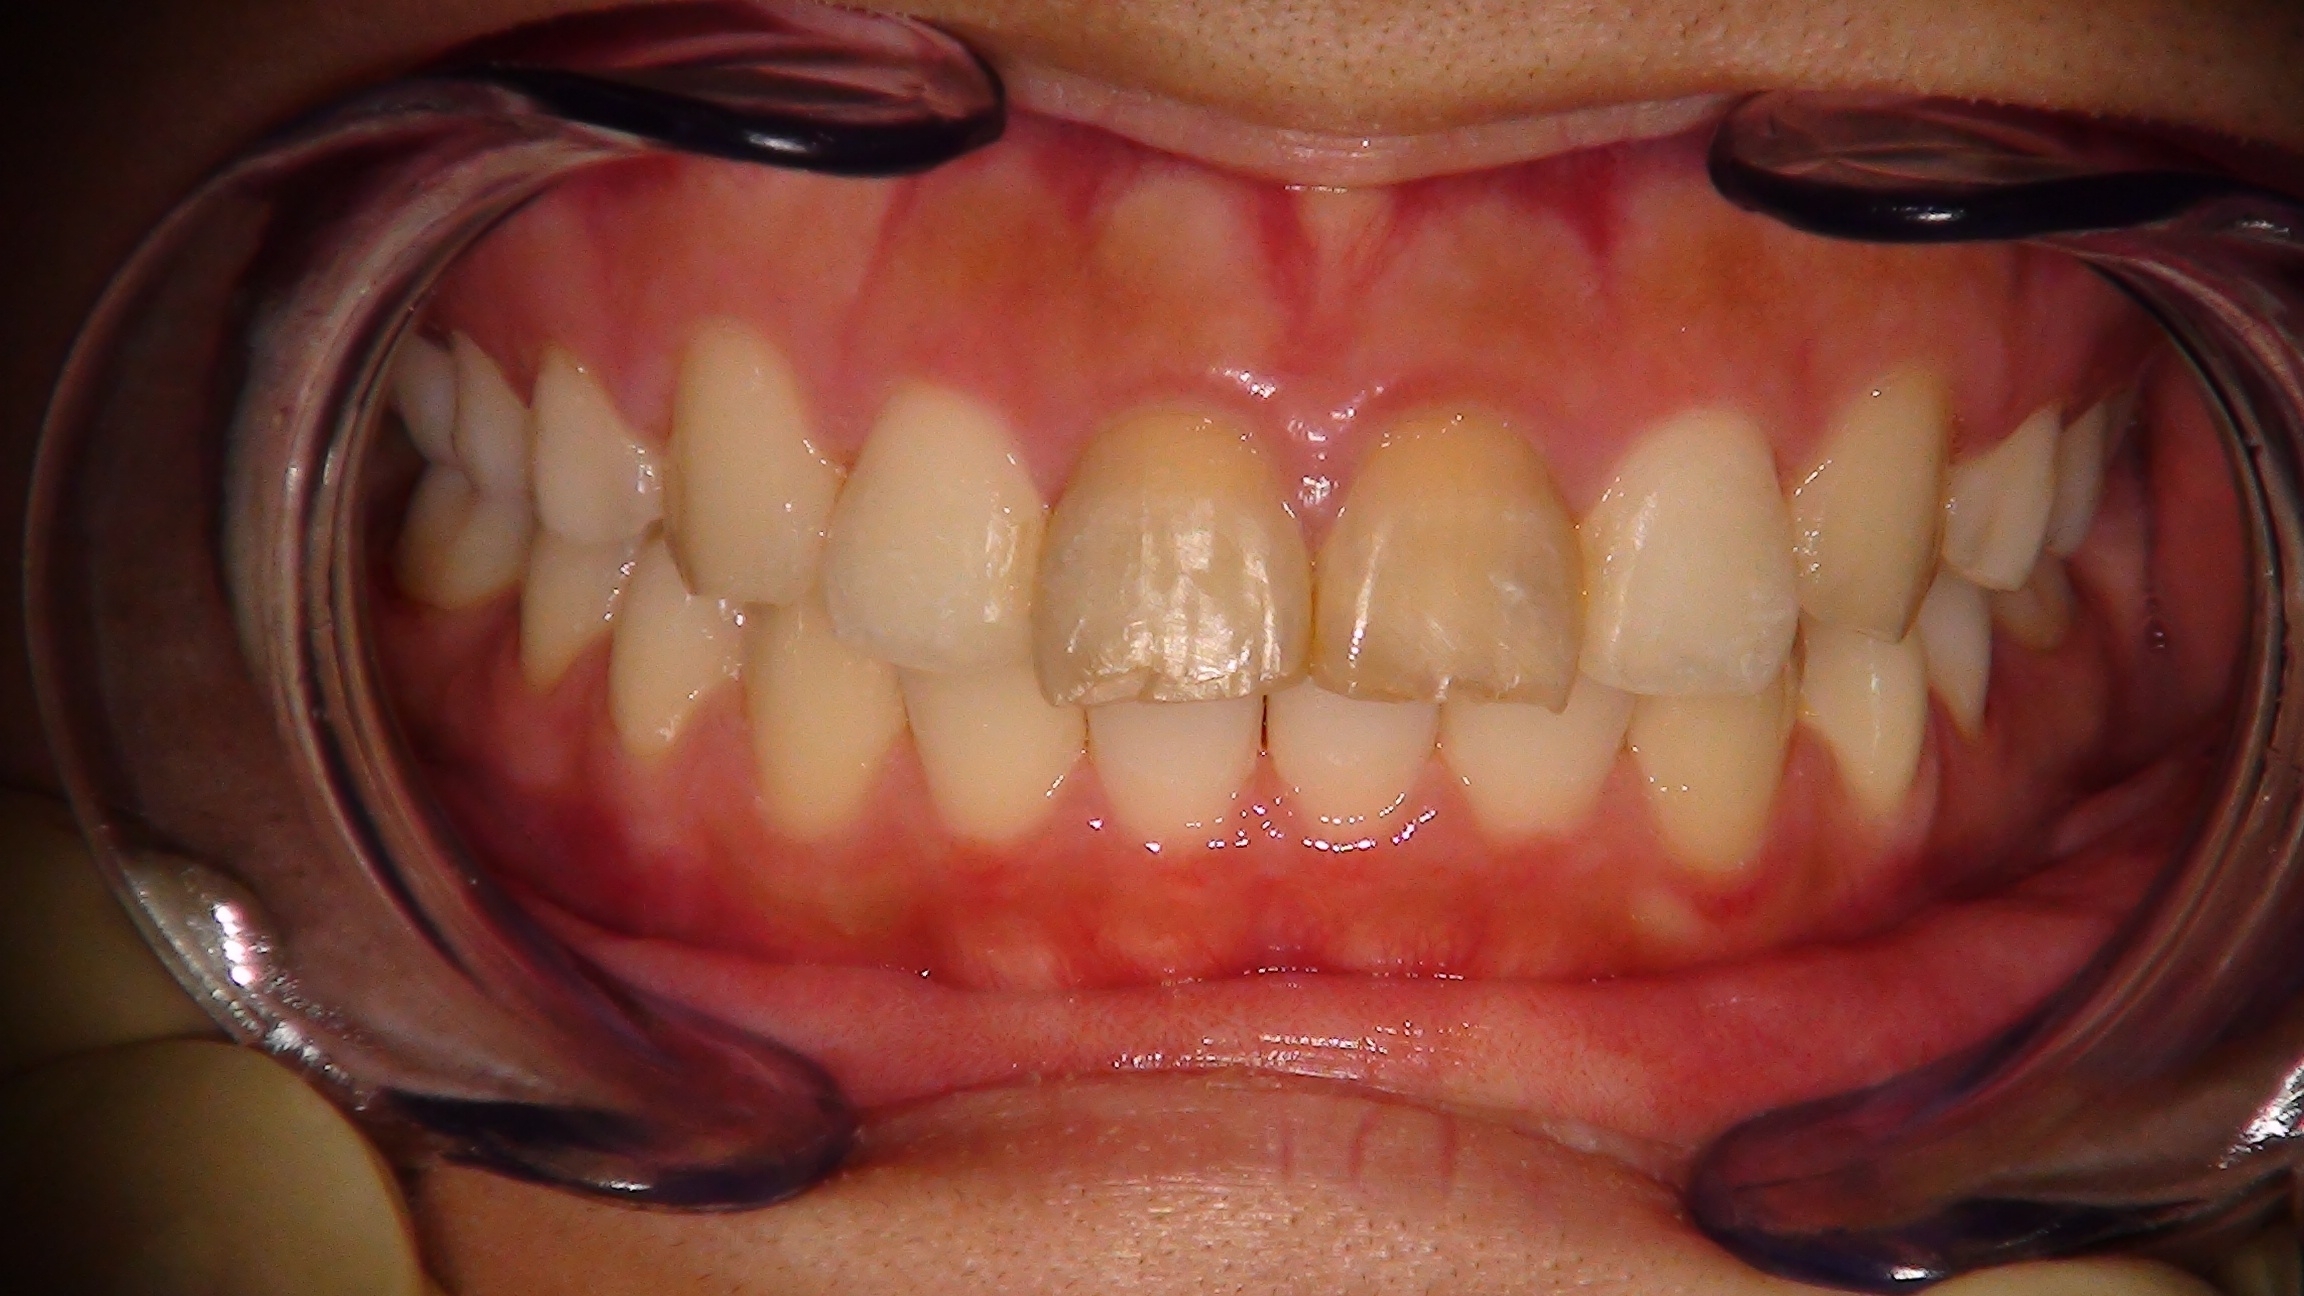

- 叢生(歯が歯列からはみ出したり重なり合ってしまったりしている場合)

- 開咬(前歯が噛みあわないような場合)など

4. 大臼歯や前歯の圧下が可能

インプラント矯正では、これまで困難だった圧下(歯を骨の中に沈めるように動かす)が可能となり、自然な笑顔や開咬の改善もできるようになりました。